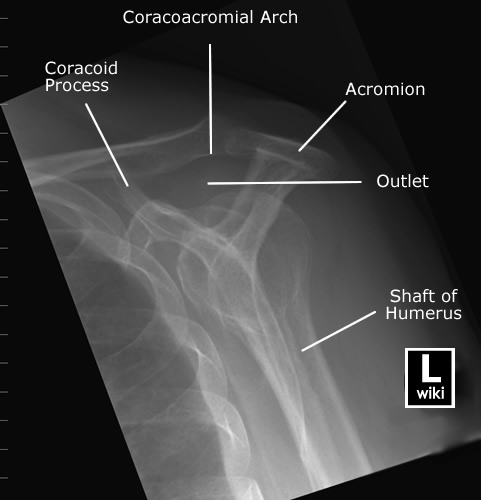

Spine Radiographic Anatomy

| AP view (Cervical) | AP view (Thoracic) |